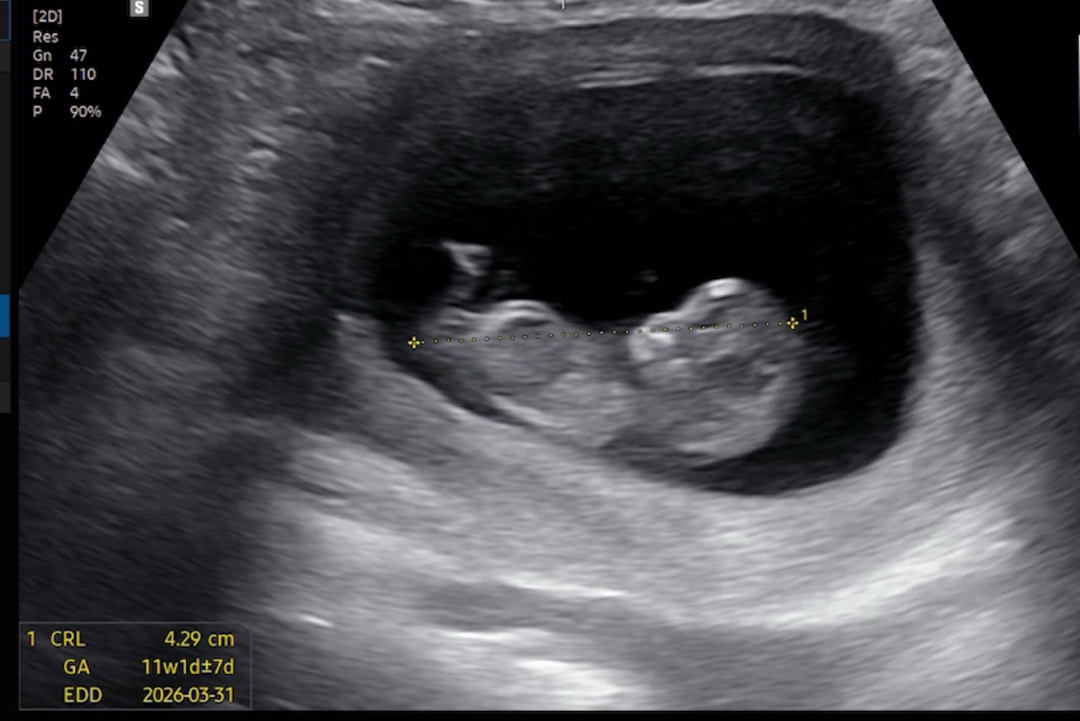

10주-11주 각도법 ...

첫째아들이라 둘째 딸을 강력크하게원하는데...ㅎ 아직잘안보이겠지만 한번봐주시면 감사하겠습니당 ! 👏🏻

잘안보여서 확인이 어려워용 ㅠㅠ

아예 생식기가 안보이네요ㅜㅜㅠ

최소 12주는 돼야해요